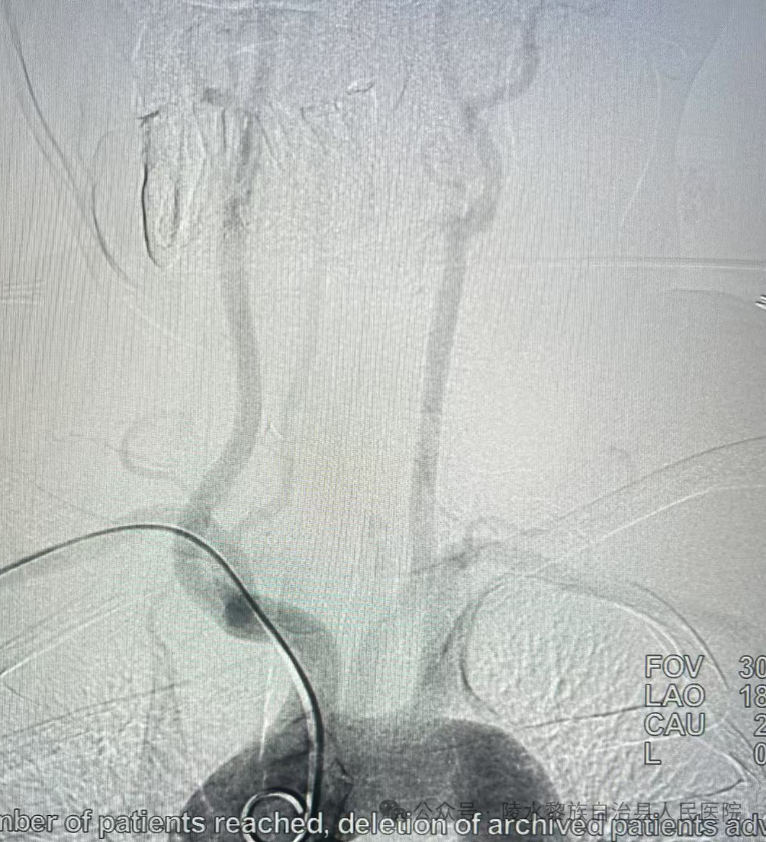

(陈浩专家与顾贤志主任为患者实施经远桡动脉穿刺全脑血管造影术)

近期,青岛大学附属医院海南分院/陵水黎族自治县人民医院神经内科团队在海南医科大学第一附属医院陈浩专家指导下,以及神经内科顾贤志主任的共同配合下,成功开展经远桡动脉穿刺全脑血管造影术,填补了陵水县在脑血管检查领域的技术空白。此项技术的应用,为本地患者开启了更为微创、安全的诊疗新篇章,让群众在家门口即可获得高质量的医疗服务,极大地提升了就医体验。

与传统经股动脉穿刺相比,该技术具有创伤小、恢复快、并发症少等显著优势,为患者提供了更安全、更舒适的诊疗体验。这一成果不仅标志着陵水县人民医院在脑血管疾病诊疗领域的技术突破,也为实现“一般病在市县解决”的目标奠定了坚实基础。